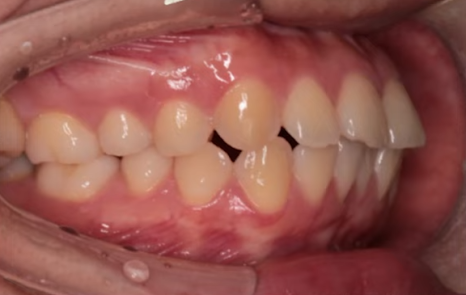

"입이 나와 보여요"라며 찾아주신 여성 환자분이셨는데요.

치료 전 X-ray 측면 모습으로도 치아가 앞으로 기울어져 있고,

상악, 하악 각각 첫 번째 소구치를 발치했고,

인비절라인을 통해 치아를 뒤로 이동시키며 돌출을 점진적으로 개선했습니다.

뻐드러져 있던 치아 배열 모습이 정상적으로 돌아온 걸 확인하실 수 있을 겁니다.

기울어졌던 앞니가 정상 각도로 줄어들었고 자연스레 돌출입도 개선된 걸 볼 수 있지요.

입술 라인도 부드럽고 자연스럽게 닫히며,

잇몸 노출도 줄어들어 웃는 인상까지 부드러워졌는데요.